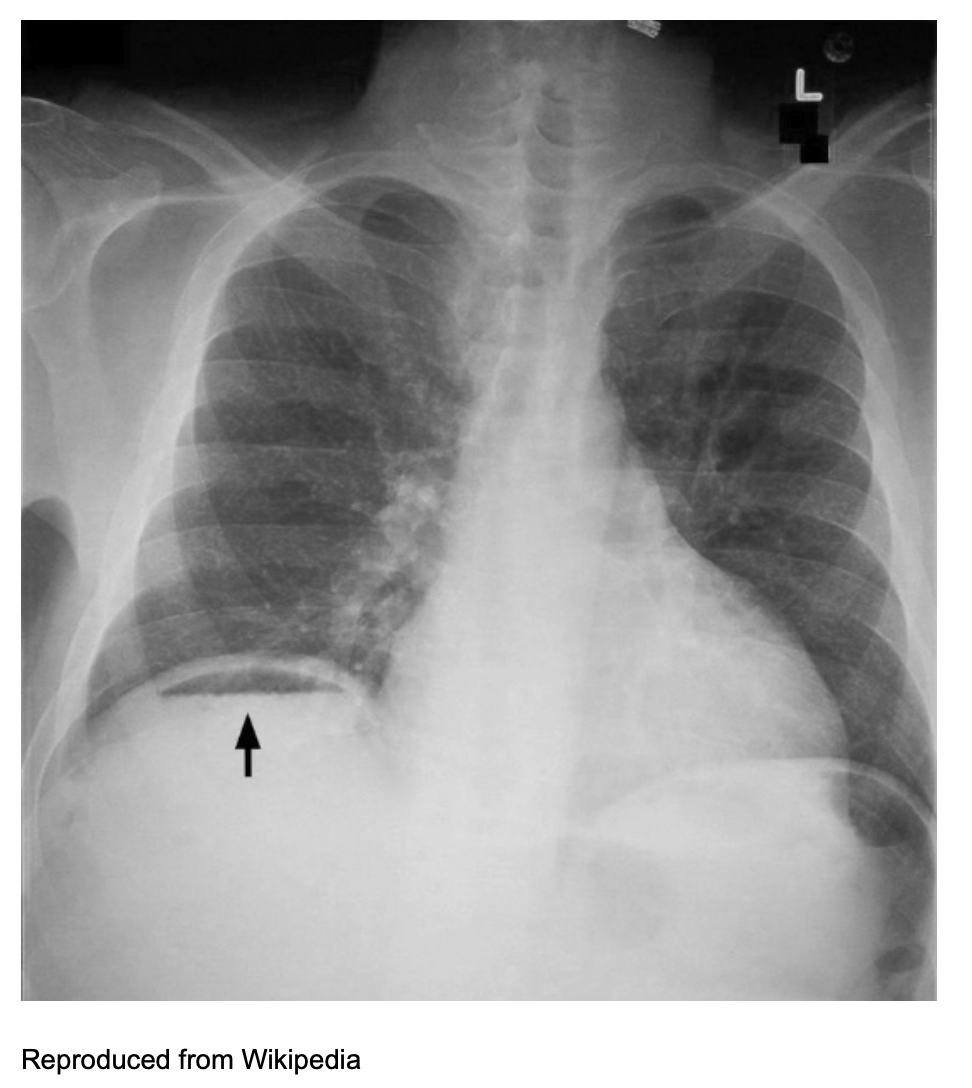

What imaging modality is used to diagnose pneumoperitoneum?

An upright chest or three-view abdominal x-ray is used to detect air under the diaphragm, which is pathognomonic for pneumoperitoneum.

What are the key differentiating factors between pneumoperitoneum and peritonitis?

Pneumoperitoneum is diagnosed radiologically (air under diaphragm), while peritonitis is a clinical diagnosis with supporting laboratory and imaging findings in the absence of pneumoperitoneum.